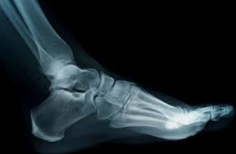

| 복숭아뼈 부음 치료방법

물혹의 경우에는 주사기로 물을 빼주는데 이러한 방법은 근본적인 치료 방법이 아니기 때문에 재발이 잘되고 자주 물을 빼내줘야하는 번거로움이 있습니다. 점액낭염이라면 소염제등 염증을 없애주는 약을 처방받아 복용하기도 합니다. 관절 누공이라면 뼈에 문제가 생긴 것이기 때문에 정형외과에서 진단을 받으시고 치료를 받는것이 좋습니다.